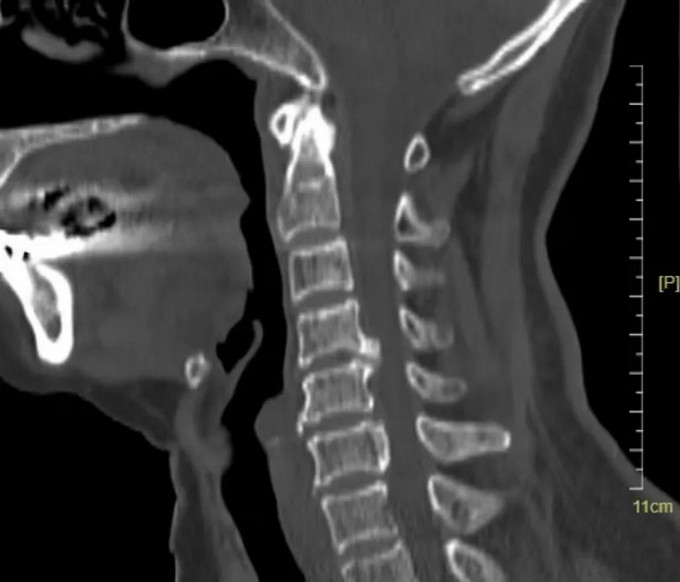

術前影像

頸椎CT矢狀位

頸椎CT橫斷位 可以看到明顯突出的骨贅